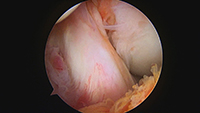

関節鏡下半月板縫合術/関節鏡下半月板切除術

特殊な縫合テクニックや器材により従来修復困難であった断裂に対しても積極的に縫合を行っております。先天的な問題である円板状半月板に対する治療経験も豊富にあります。

半月板縫合の関節鏡画像